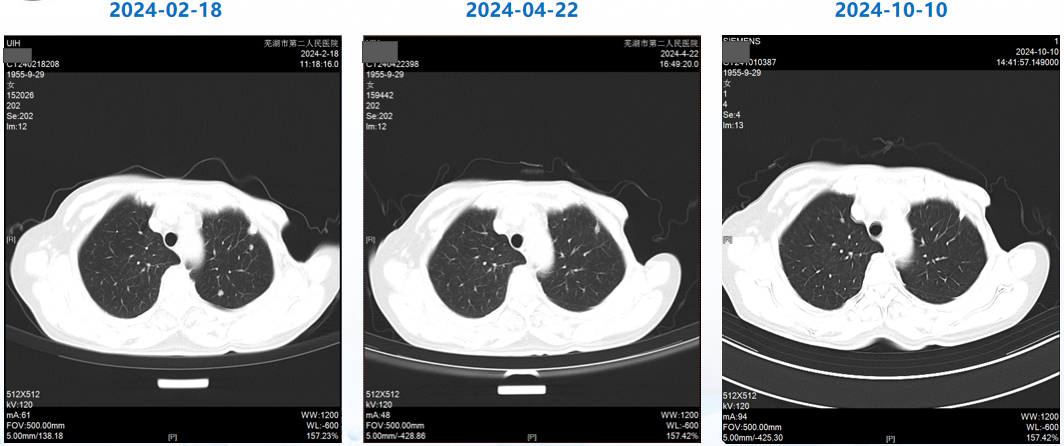

治疗3个周期后(2024-04-22),患者复查CT,肺转移灶、肝转移灶疗效评估达PR,至末次复查(2026-01-12)时评价为疾病稳定(SD),目前患者仍在继续T-DXd治疗;治疗期间未出现间质性肺病(ILD)/肺炎相关症状,甲状腺减退症状经对症处理后较前好转(促甲状腺素:4.695 mIU/L)

△患者肺转移灶影像变化